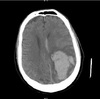

Seorang wanita 22 thn dengan sakit kepala dan pemeriksaan neurologis non-focal selama trimester akhir kehamilan pertama. CT-scan kepala ditampilkan. Intervensi segera paling tepat adalah :

The hemorrhage pattern visualized is the harbinger of a dural sinus thrombosis (DST). DST is an uncommon problem that can present benignly and rapidly deteriorate into a devastating and life threatening situation. Early recognition and intervention, even in stable patients, is is essential to improve outcome.

Venous stasis secondary to dural sinus thrombosis leads to a characteristic “flame Shaped” parenchymal hemorrhage with edema that resembles a contusion, usually in a lobar distribution, near a major venous sinus. Occasionally, asymmetric hemispheric edema can occur without hemorrhage, if there is adequate collateral venous drainage.

In the stable patient, immediate anticoagulation with heparin is indicated. This includes patients with a neurological deficit who are not deteriorating. Gradual titration to to a therapeutic PTT (2 - 2.5 times normal) without a loading bolus has been shown to be effective with low risk.

Corticosteroids are not indicated because edema related to DST is cytotoxic rather than vasogenic. Furthermore, corticosteroids can promote hypercoagulability.

Craniotomy should be avoided at all costs in these patients. Venous stasis related to DST increases the risk of uncontrollable intraoperative hemorrhage. Hematoma enlargement following surgery is common.

Mannitol can be used as a temporizing measure when malignant intracranial hypertension is present. In this patient, however, the neurological exam is intact and the scan shows only surrounding edema without significant shift. There is no evidence that the rheological properties of low dose mannitol are beneficial in DST.

Intracranial pressure monitoring may be helpful in the management of patients with DST. In this patient however, the neurological exam can be used as a sensative indicator of deterioration. Some clinicians would consider inserting a monitoring device prior to initiating anticoagulation therapy. A fiberoptic subarachnoid monitor would be preferrable to a ventriculostomy to avoid transgressing the brain parenchyma.